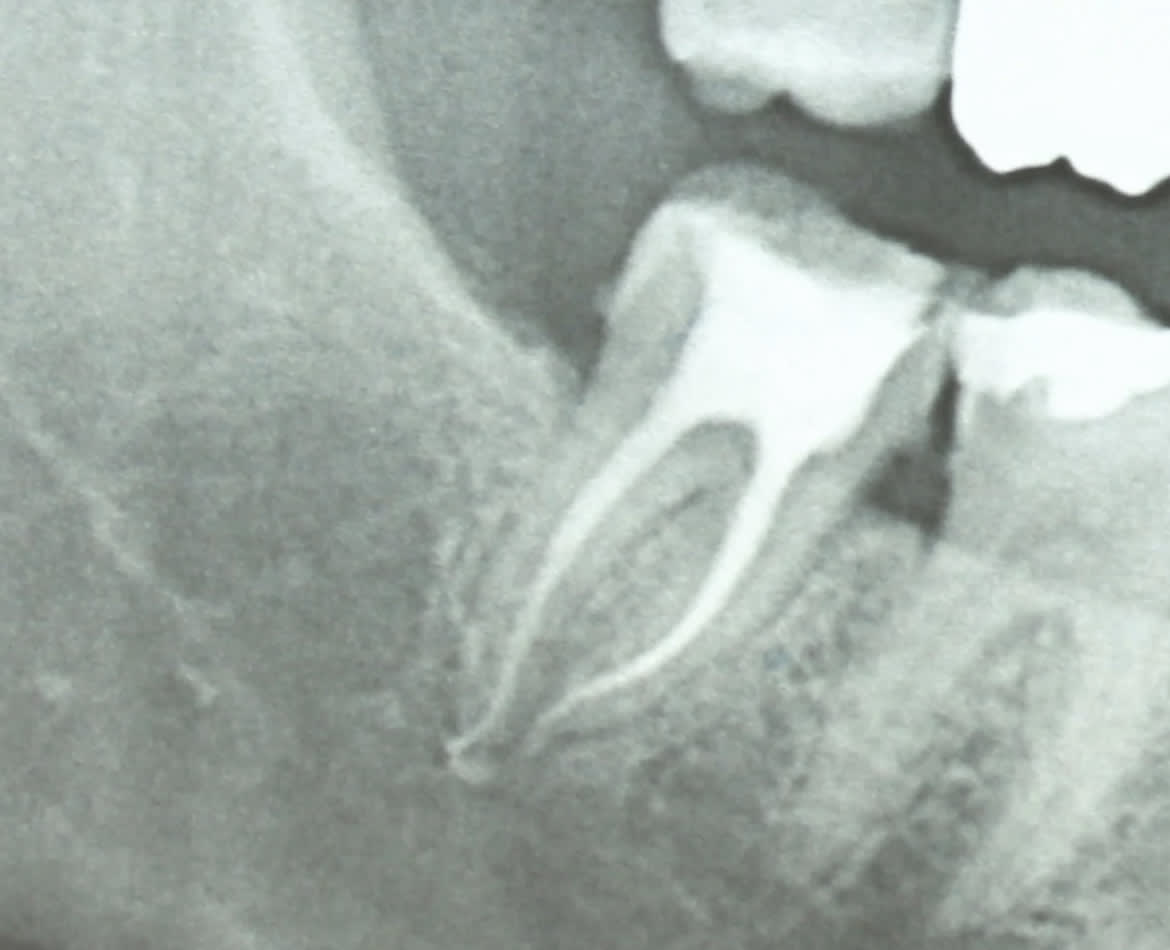

Pour moi aucune image osseuse radio nulle part; juste ton anatomie osseuse plus ou moins dense/épaisse.

Et sinon si on veut parler sérieusement : dépassement de pâte et du cône racine D .

De pâte oui mais pas de cône .